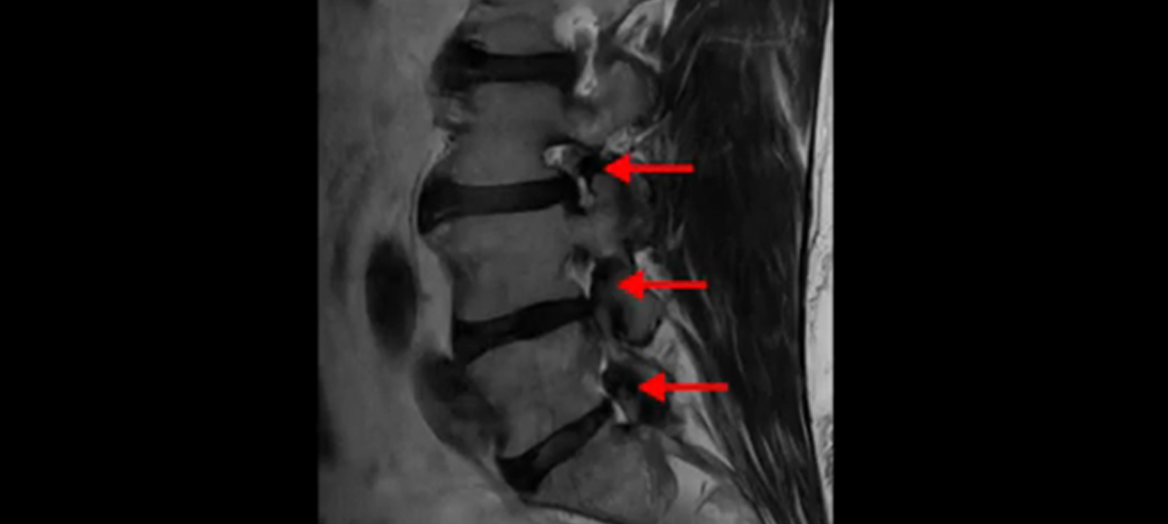

이분 MRI를 잠깐 보실까요? 보시면 두 마디가 특히 안 좋은데 3번 4번 디스크가 터져서 흘러 내려 있습니다.

보시다시피 흘러 내려온 디스크 수핵이 신경 공간의 왼쪽으로 보입니다.

그런데 이분은 4번 5번에도 디스크 파열이 있습니다.

가운데로 심하게 밀려 나와 있는데요.

또 4번 5번에는 협착으로 척추관이 많이 좁아져 있습니다.

또 왼쪽 신경 가지들이 빠져 나가는 신경구멍들이 여러 마디가 좁아져 있습니다.

이런 이유들 때문에 왼쪽 엉덩이부터 종아리, 발가락까지 저리고 아픈 겁니다. 그래서 서둘러 병원에 가셨는데요. 그래서 서둘러 병원에 가셨는데요. 여러분이 꼭 아셔야 할 게 이렇게 다리가 심하게 저리고 아프면 X-ray만 찍을 게 아니고 MRI를 찍어 보시는 게 맞습니다. X-ray로는 디스크가 터졌는지 신경구멍이 좁아진 협착이 있는지를 정확히 할 수가 없습니다. 그래서 이분은 당장 아픈데 해결이 안 되니까 제주도에서 유명하다는 한의원으로 갔습니다.